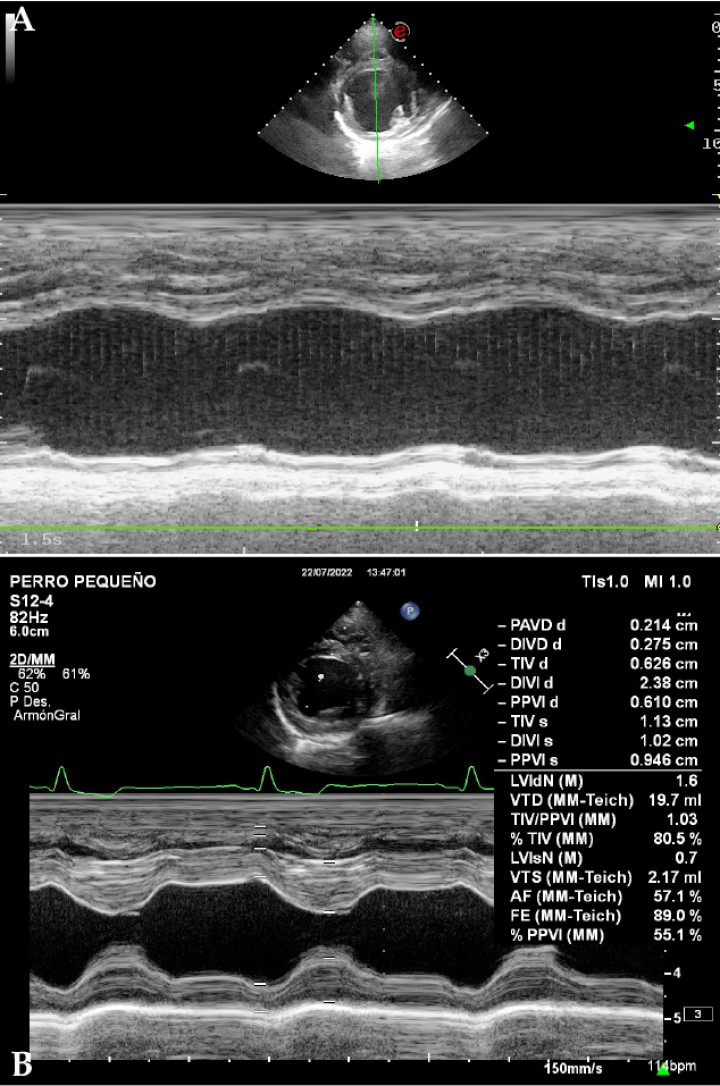

<p>(<strong>A</strong>) Imagen ecocardiográfica en modo M, paraesternal derecha en eje corto a la altura de los músculos papilares del ventrículo izquierdo de un perro con cardiomiopatía dilatada. Nótese la ausencia de contracción ventricular en comparación con la misma imagen en un paciente sano. (<strong>B</strong>) Imagen ecocardiográfica en modo M, paraesternal derecha en eje corto a la altura de los músculos papilares del ventrículo izquierdo de un perro sano. Se observa el diámetro del ventrículo izquierdo en diástole normalizado (LVIDn) con un valor de 1,6. Este es un valor normalizado del diámetro de ventrículo izquierdo en diástole (LVIDD) en función del peso mediante la siguiente fórmula: LVIDn= LVIDD / Peso 0,294. El valor de referencia se sitúa por debajo de 1,7 cm.</p>

Figura 6

(A) Imagen ecocardiográfica en modo M, paraesternal derecha en eje corto a la altura de los músculos papilares del ventrículo izquierdo de un perro con cardiomiopatía dilatada. Nótese la ausencia de contracción ventricular en comparación con la misma imagen en un paciente sano. (B) Imagen ecocardiográfica en modo M, paraesternal derecha en eje corto a la altura de los músculos papilares del ventrículo izquierdo de un perro sano. Se observa el diámetro del ventrículo izquierdo en diástole normalizado (LVIDn) con un valor de 1,6. Este es un valor normalizado del diámetro de ventrículo izquierdo en diástole (LVIDD) en función del peso mediante la siguiente fórmula: LVIDn= LVIDD / Peso 0,294. El valor de referencia se sitúa por debajo de 1,7 cm.